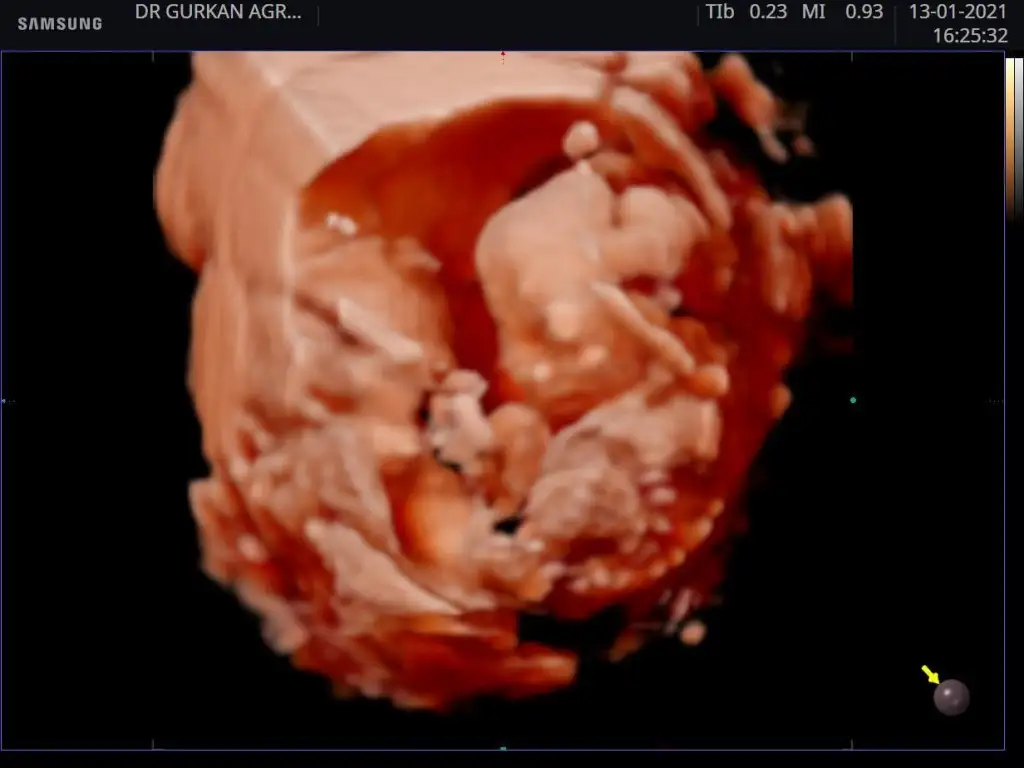

Çizen bile oldu

Eklentiler

• Screenshot_2021-01-13-18-27-03-054_com.instagram.android.webp

8,9 KB · Görüntüleme: 689

• Screenshot_2021-01-06-22-40-23-387_com.instagram.android.webp

14,8 KB · Görüntüleme: 799